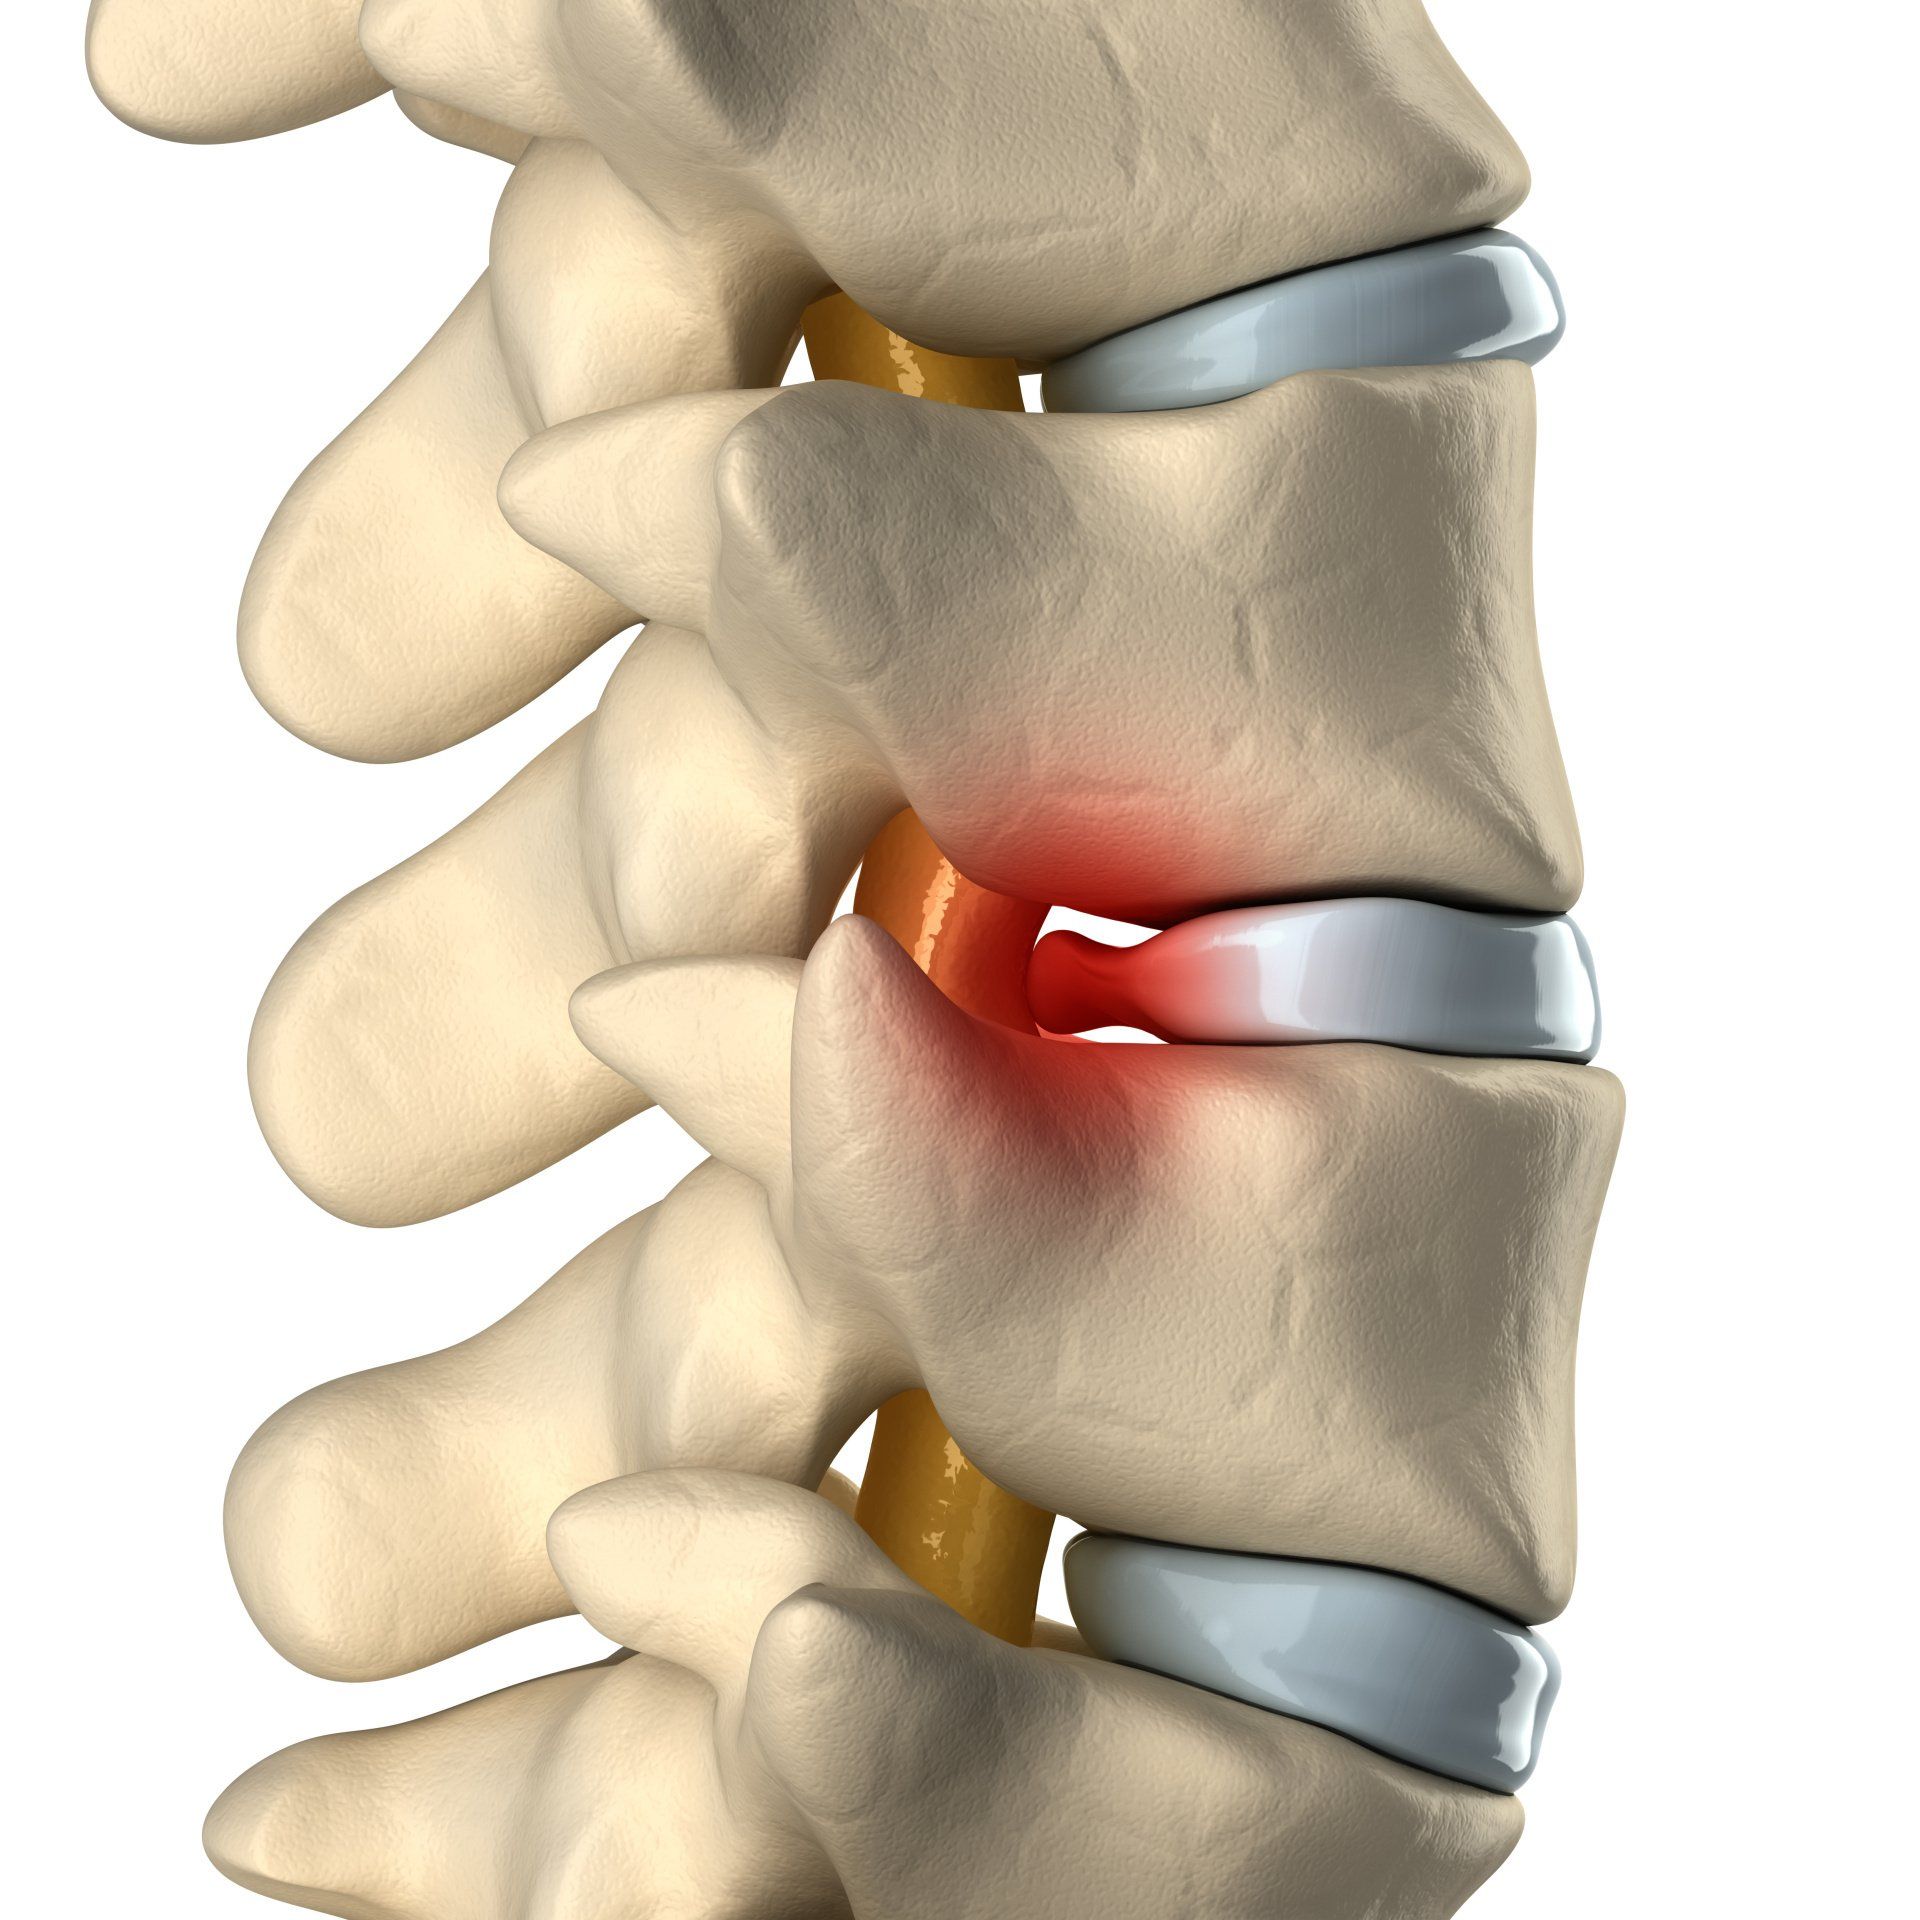

Doenças da Coluna Vertebral